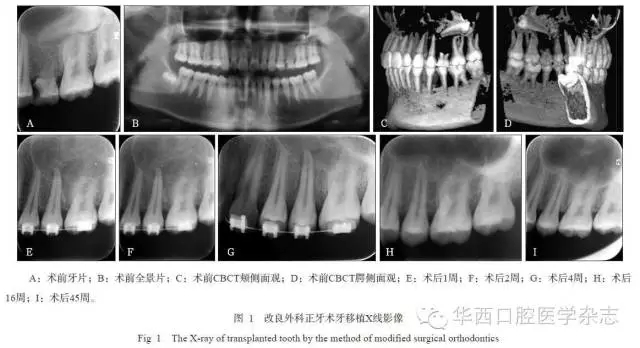

術前常規(guī)檢查,拍攝全景片或口腔頜面錐形束CT,根據(jù)需要取研究模型,分析供牙與受區(qū)情況,主要包括供牙手術完整取出的評估;供牙大小、形態(tài)、牙根數(shù)目、彎曲程度等,與受區(qū)吻合度的評估;移植牙愈后及鄰牙損傷的評估;以及受區(qū)骨量等。術前測量受區(qū)間隙近遠中寬度大于等于供牙牙冠近遠中寬度,否則,正畸擴大間隙或術中鄰面片切減徑。牙槽骨缺損或骨量不足備人工骨粉(Bio-oss或倍骼生)。

牙移植術后,均采用正畸片段弓或正畸弓絲黏接固定4~6周,術后定期隨訪6個月以上,觀察移植牙愈合狀況及X線影像改變。在術后2~12周,根據(jù)牙周愈合狀況、牙冠色澤的變化、電活力測試與X線根尖區(qū)影像等綜合評估,酌情判斷是否進行根管治療。

45例移植牙經(jīng)過手術異位移植、正畸固定4~6周后,逐漸獲得穩(wěn)固,并行使咀嚼功能。經(jīng)0.5~2年的隨訪觀察,34例移植牙均未出現(xiàn)牙根吸收、牙齒松動等并發(fā)癥,達到成功標準;11例移植牙中存在松動小于Ⅱ度、移植牙類牙周膜影增寬、牙槽骨楔形吸收、牙根吸收(但小于等于2.0?mm)等一項或幾項情況,能承擔部分咀嚼功能,達到有效標準。隨訪期內(nèi)未見失敗拔牙病例。

2組移植牙術后6個月的臨床和影像結(jié)果見表1和2。統(tǒng)計分析表明:1)A、B組的松動度、根管治療比率有統(tǒng)計學差異(P=0.021, P=0.025),而牙冠色澤變化、電活力測定無統(tǒng)計學差異(P=0.225, P>0.05)。2)A、B組的移植牙根吸收、牙槽骨吸收有統(tǒng)計學差異(P=0.025,P=0.038),而牙周膜影像改變無統(tǒng)計學差異(P=0.169)(表2)。A組療效優(yōu)于B組。